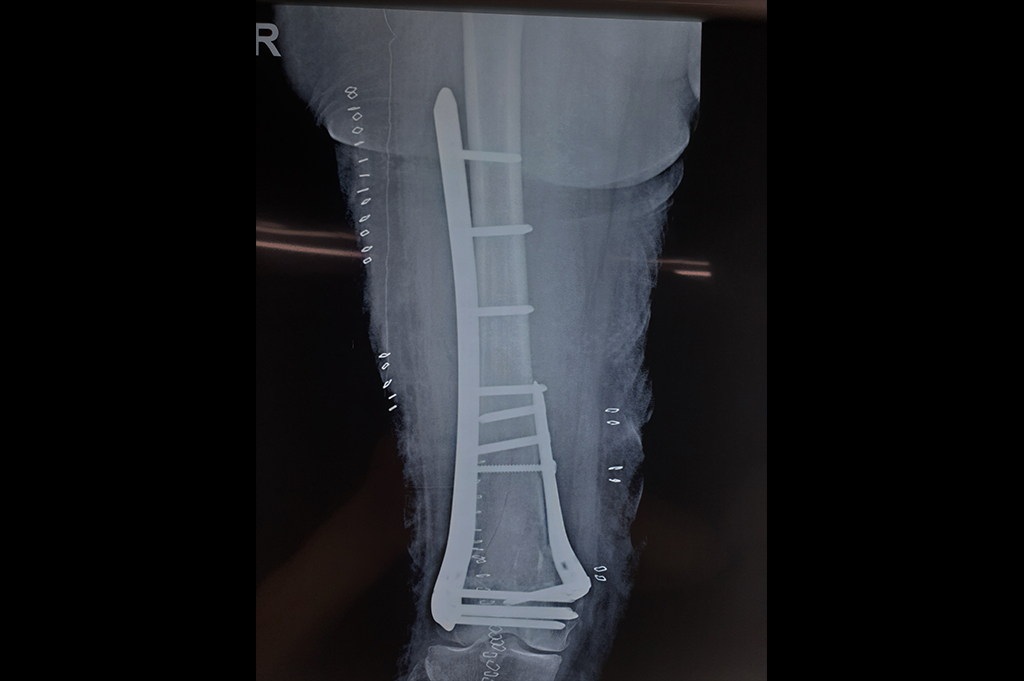

Tibia Nailing